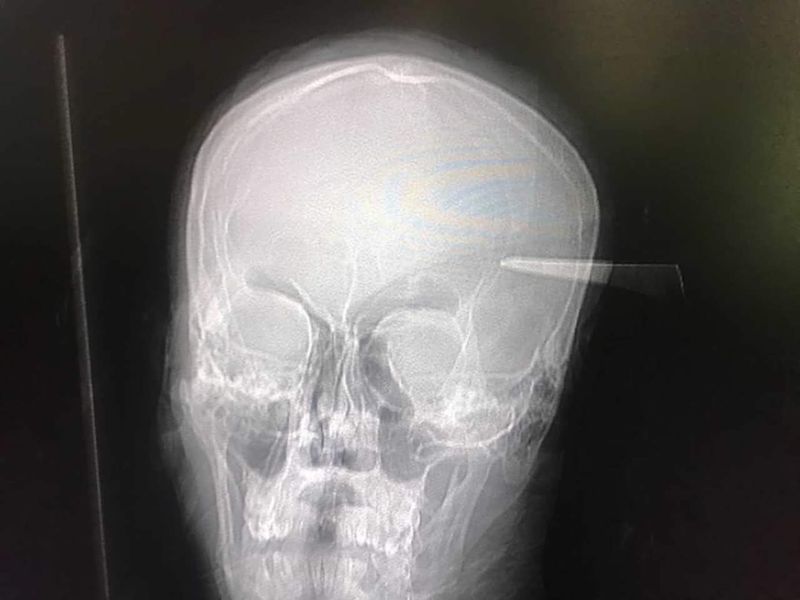

23 year old male presented after being stabbed by his brother in the head for wearing his T-Shirt without permission. Upon presentation his GCS was 15/15 with no neurological deficit. CT-B and CT-Angio suggested no major vascular involvement. Blade was removed with C-Clamp and mallet under general anesthesia with no active bleeding. GCS remained 15/15 post operatively and repeat CT-B revealed no extra-axial or intra-axial bleed or tractoma.